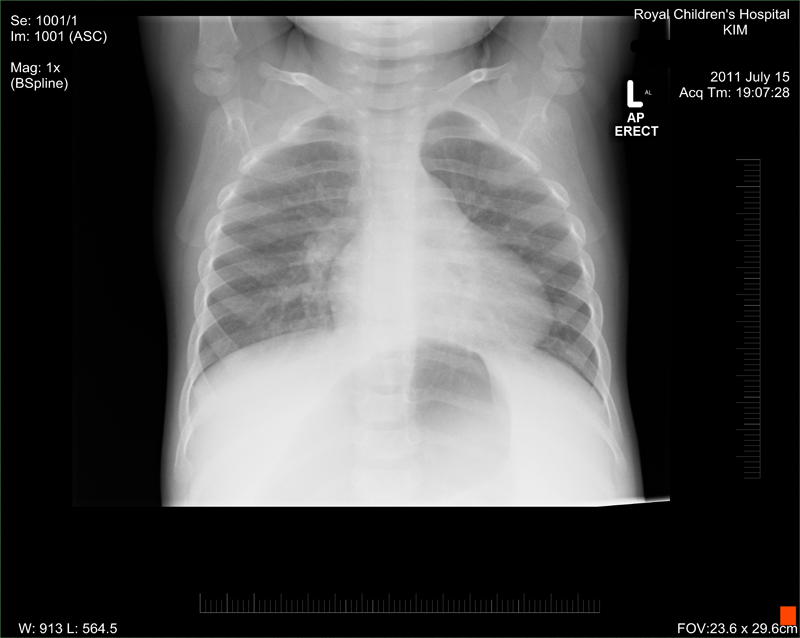

Emergency Royal Children's Hospital emergency organise an X-ray and some blood tests etc. The X-ray confirms a mass but it is not clear what it is, it only tells that there is something wrong. Later they organise her to be admitted. (We didn't know it but from that day on the hospital was becoming our new home.)